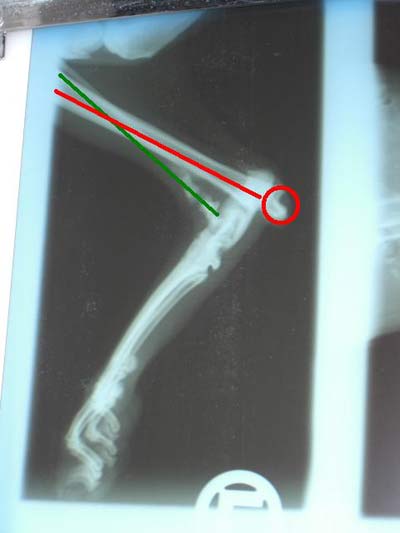

Jule wurde mit einem komplizierten

(offenen und schon älteren) Bruch am

Hinterlauf gefunden (siehe Röntgenbild)

und muss nun in der Tierklinik operiert werden,

da sie unter starken Schmerzen leidet. Erst

unter Narkose kann entschieden werden, ob

das Bein versteift werden kann, oder ob es

amputiert werden muss.